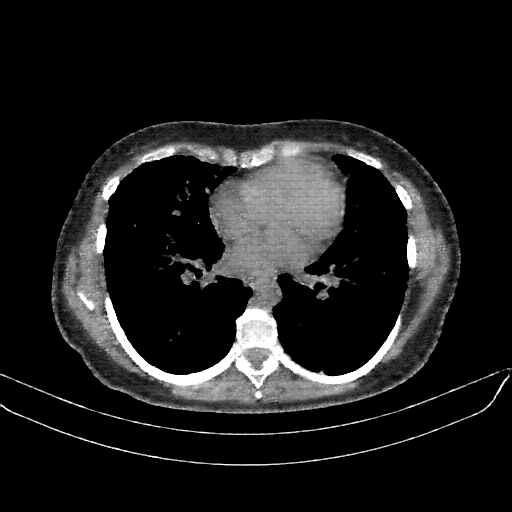

Targeted Slice 70 - Mediastinum Window Analysis (Generated vs Real Venous)

0.762

Mediastinum SSIM

47.9

Mediastinum RMSE

17.1

Mediastinum MAE

Average Mediastinum Window Metrics Across All Slices (133 slices) - Generated vs Real Venous

0.740

Mediastinum SSIM (Avg)

46.9

Mediastinum RMSE (Avg)

17.0

Mediastinum MAE (Avg)

Original NATIVE CT scan (input)

Mediastinum window (WL 40, WW 400 β†’ Low βˆ’160, High +240)

Reconstructed NATIVE CT scan (cycle consistency)

No window - Raw intensity values